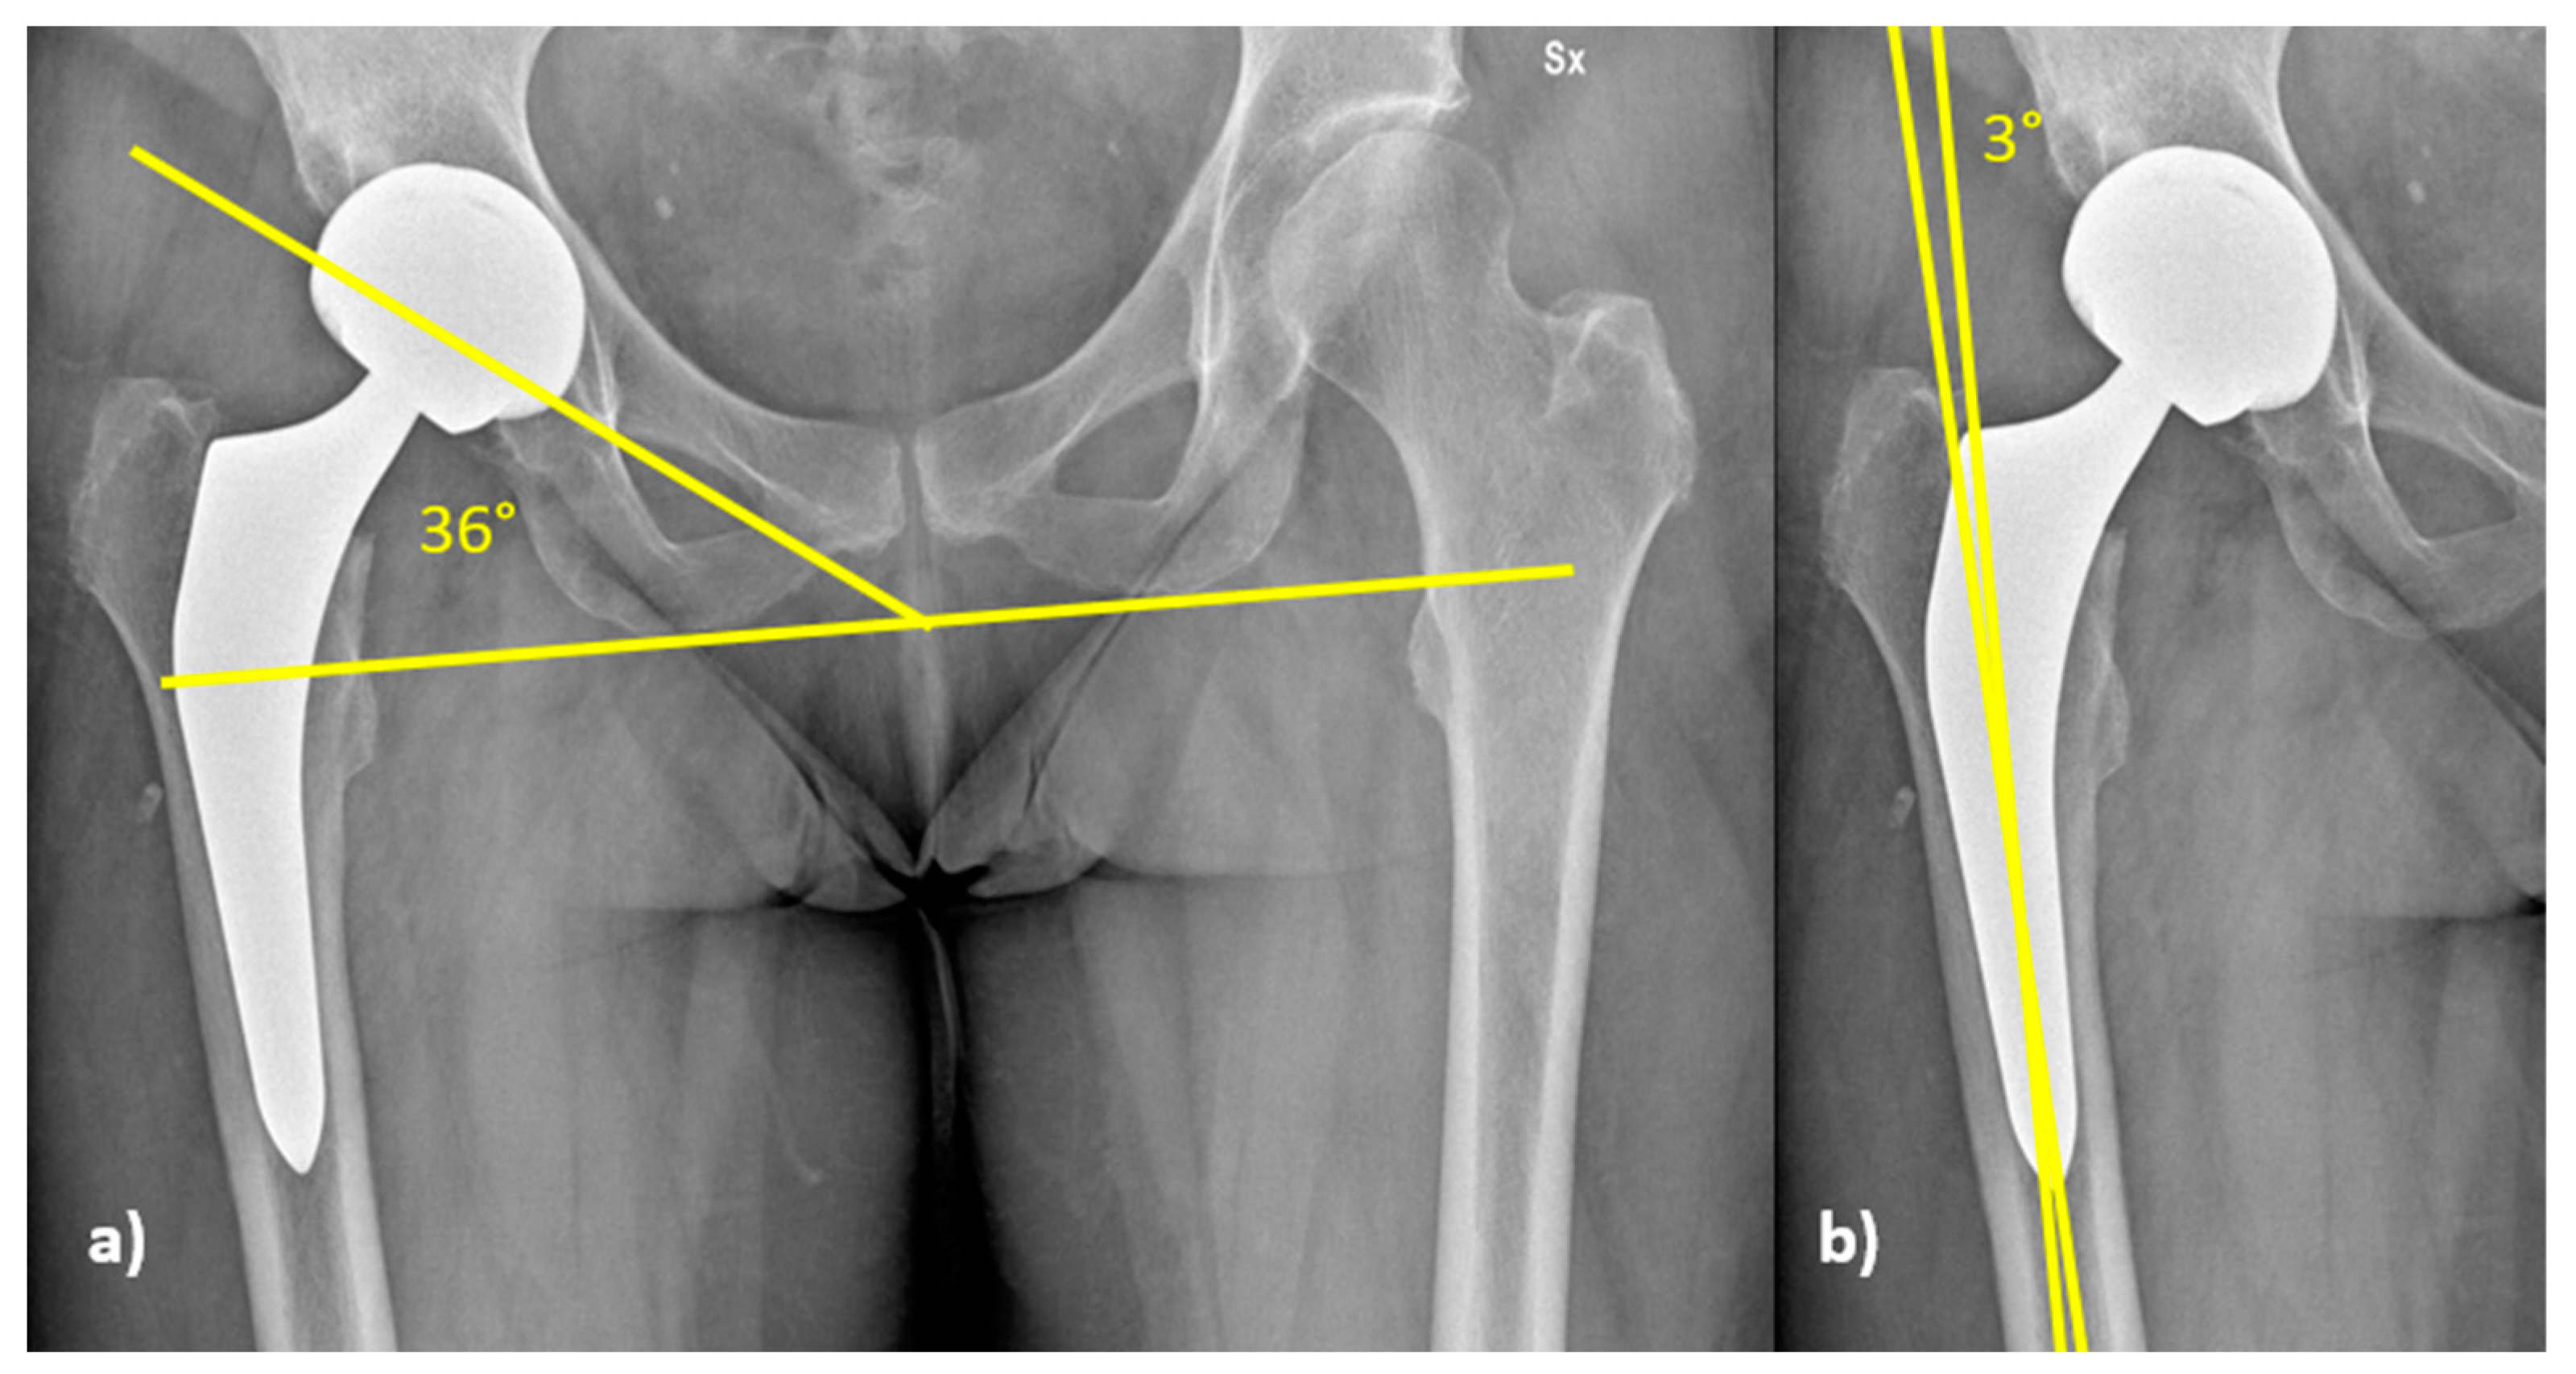

3.2. Radiographic Analysis

| Within Lewinnek’s safe zone | 74 (77.1%) | 86 (74.8%) | 62 (75.6%) | 222 (75.8%) |

| Out of Lewinnek’s safe zone | 22 (22.9%) | 29 (25.2%) | 20 (24.4%) | 71 (24.2%) |

| Total | 96 | 115 | 82 | 293 |